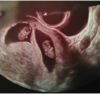

U nas wszystko Oki widzieliśmy rączki nóżki ruszają ślicznie nimi. Kolejna wizyta za 3 tygodnie.

Ja idę w piątek na wizytę mam nadzieję że też będą takie piękne widoki... My mniej więcej idziemy równo który to tydzień dzisiaj? Między nami tylko był jeden dzień różnicy w transferze... A jakie miałaś USG dopochwowe czy przez brzuch?